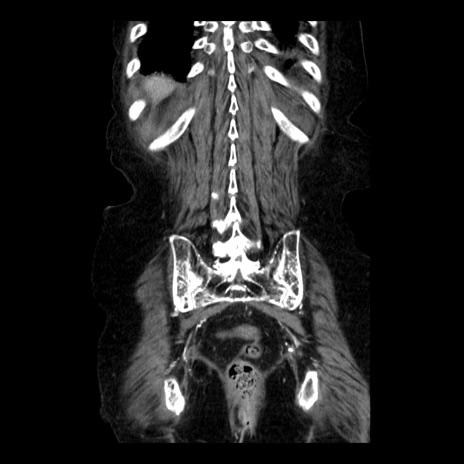

症例14(冠状断像)

【症例】 90歳代女性

【主訴】 腹痛・嘔吐

【現病歴】今朝から左側腹部痛を認めた。 経過観察していたが、嘔吐を認めたため来院。

【既往歴】 子宮癌術後

【身体所見】 意識清明、BP 127/54mmHg、P 98bpm Sp02 95%(RA)、BT 35.8°C、腹部平坦・軟腸ぜん動音聴取良好、右下腹部圧痛(+) 反跳痛なし

【データ】WBC 9800、CRP 0.46